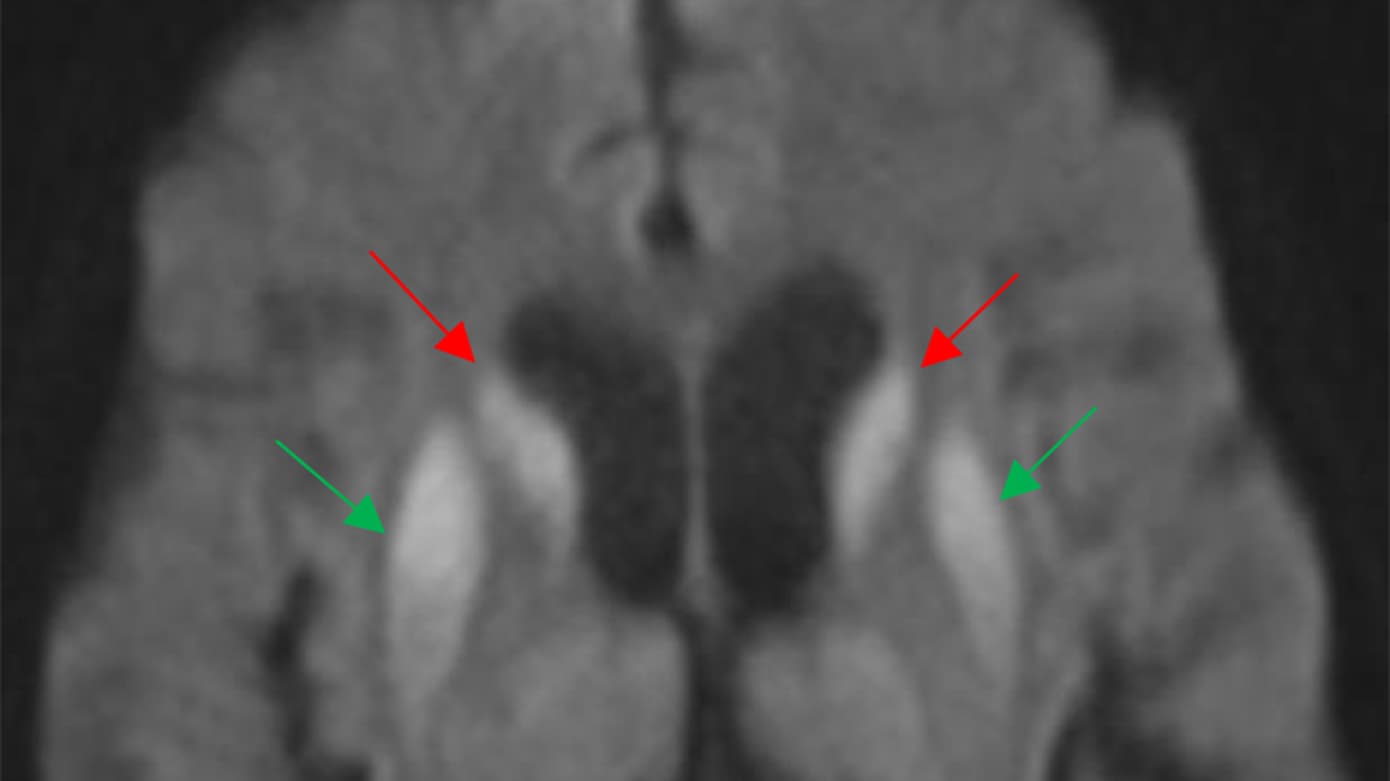

I forbindelse med faldudredning udførtes MR-skanning af hjernen, som viste isolerede hyperintense signaler med kraftig diffusionsrestriktion svarende til nucleus caudatus og nucleus lentiformis (basalganglierne) på begge sider (Figur 1). Hun blev derfor overflyttet til Neurologisk Afdeling, hvor man objektivt fandt hende uden sygdomsindsigt og med tegn fra lillehjernen, herunder opbrudte øjenbevægelser, ataksi ved finger-næse-finger-forsøg samt udtalt trunkal instabilitet som årsager til gangbesværet.

Patienten havde hurtigt udviklet visuospatiale udfordringer med manglende sygdomsindsigt samt cerebellare symptomer, og hendes MR-skanning viste klassiske tegn på Creutzfeldt-Jakobs sygdom. Da hendes RT-QuIC test var positiv, opfyldte hun kriterierne for mulig sporadisk Creutzfeldt-Jakobs sygdom.